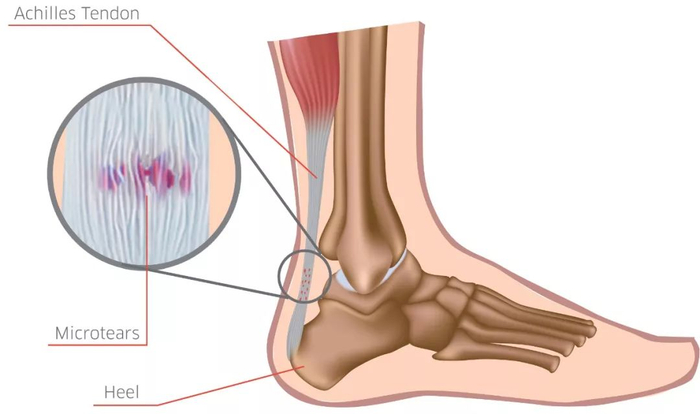

其实跟腱是众多肌腱中的最大的一个。而肌腱存在的原因,则是由于肌肉和骨骼无法直接连接,中间必须要有一个 “纽带” 来帮助它们连接到一起,肌腱就扮演了这个角色。跟腱则是帮助小腿三头肌(比目鱼肌和腓肠肌)连接到跟骨的那条“纽带”,在跑步过程中,这条 “纽带“ 可以传递高达 12 倍体重的负荷。

青年人群比较容易出现 非止点型跟腱炎 ,出现此类跟腱炎的患者,通常会在跟腱止点上方 2~6 cm 的位置出现疼痛、肿胀。这主要是因为,青年运动者多数急于训练,对疼痛不在意。有数据显示,患上非止点跟腱炎的田径运动员中,60%-80%采用错误的训练方式—太多、太急。

跟腱的过度使用,通常会造成超过生理极限的超负荷作用于跟腱,从而使跟腱出现细微损伤。开始时,这些细微损伤并不会造成明显不适。但出现损伤后的跟腱血液供应会逐渐变差,延长恢复时间,当再次训练时又会造成二次伤害,最终转变成严重损伤。其实这个过程和铁锈侵蚀整块铁非常像,开始并不起眼,但逐渐积累起来,最终却会引发断裂等情况。